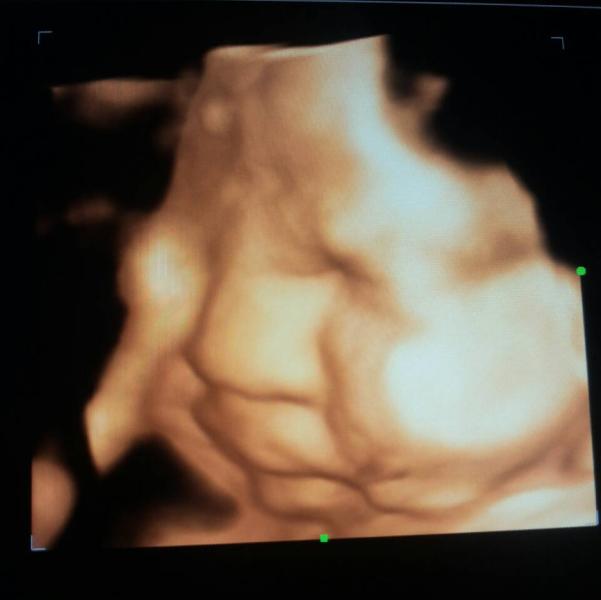

Девочки, покажите ваше узи на 36 37 недель♡♡♡ если вы делали на таком сроке♡♥

у нас 1800 дай Аллах дойду до срока пришлю. последний раз была на 22 неделе она жучка закрыла личико руками и спала

@beti он не смог нормальное сделать говорит ребенок большой уже )) 1500

Пока нет фото странное, не могли чуть яснее сделать как никак деньги за это берут у вас сколько стоит узи

@zara_z она большая же уже не поместилась